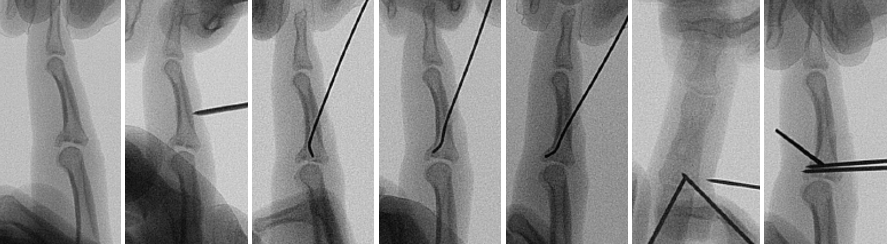

Fragestellung: Instabile Frakturen der Fingerbasis mit Gelenkflächenimpression stellen ein komplexes Trauma dar. Die Behandlung dieser Verletzungen wird in der Literatur kontrovers diskutiert, bisher konnte keine operative Behandlungsform ihre Überlegenheit zeigen. Hintringer und Ender beschrieben 1986 die perkutane Aufstopftechnik der imprimierten Gelenkfläche (s. Abbildung 1 [Abb. 1]) an vier Patienten.

Abbildung 1: Repositionstechnik mit Aufstopfdraht (von links nach rechts): Der Finger wird in Längsrichtung